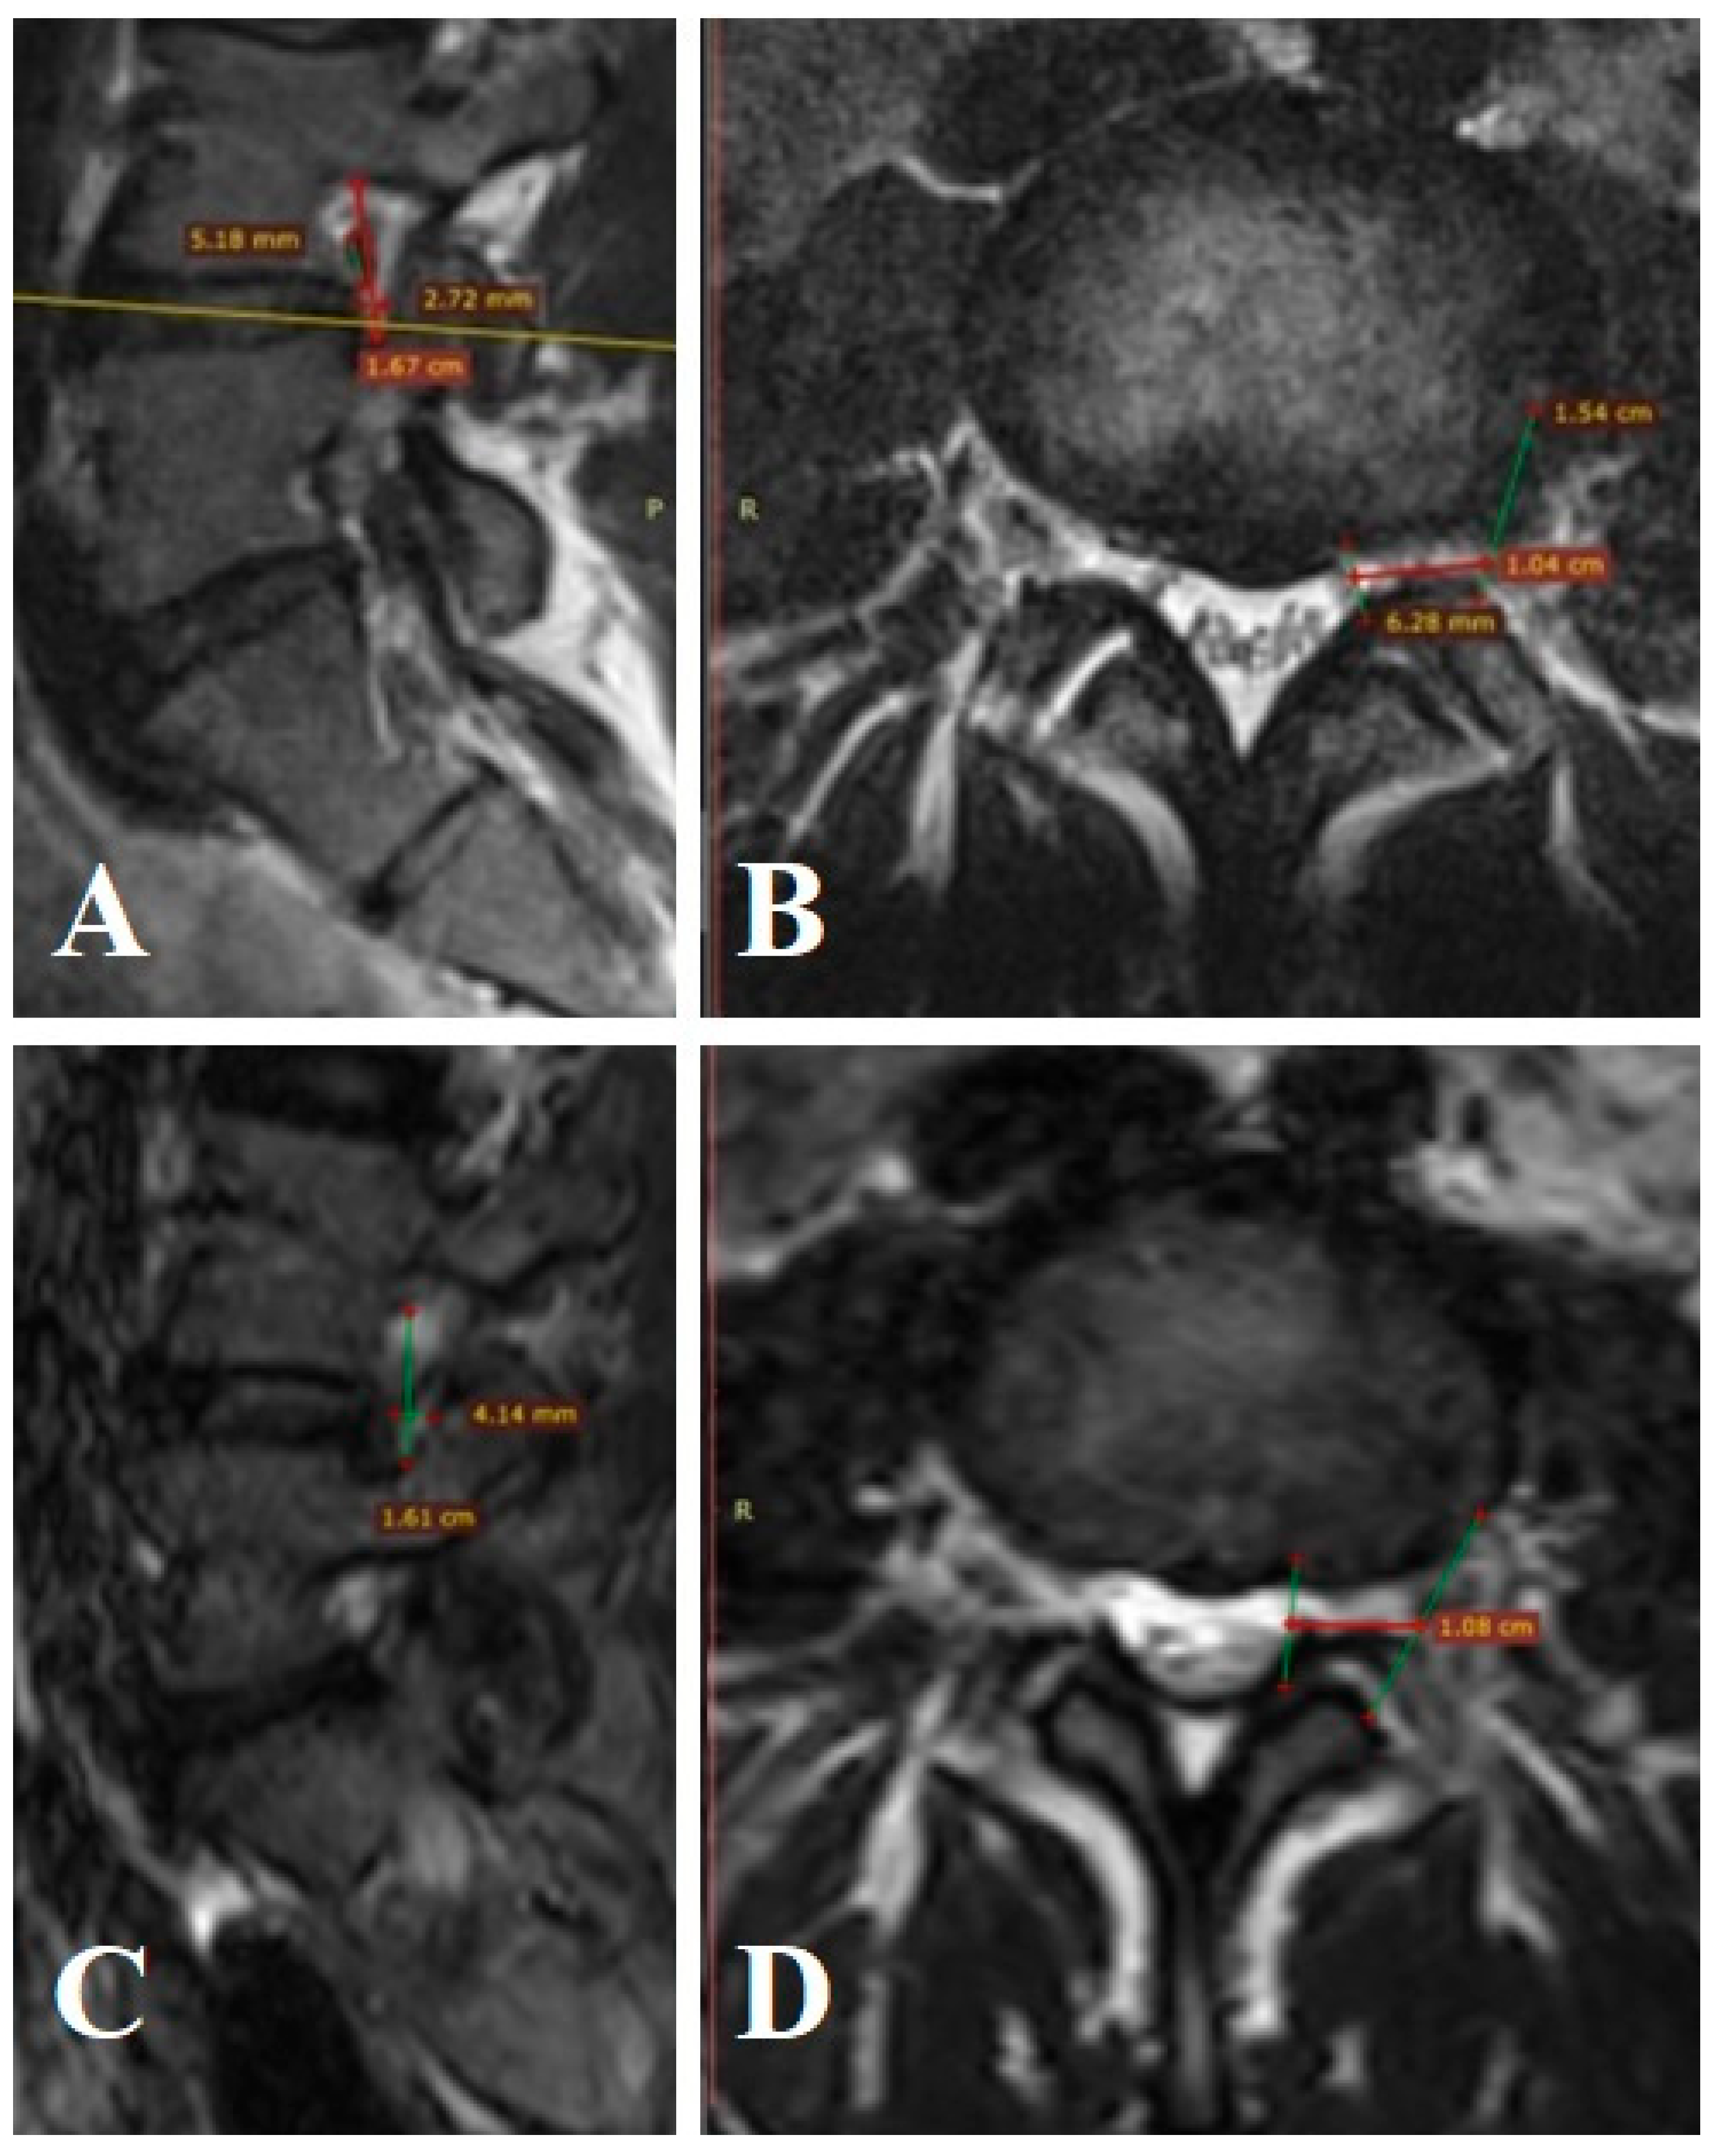

Patient n° 1 is a 27-year-old male, presented with complaints of lumbar pain radiating to the left lower limb. The pain was refractory to conservative treatment for over three months. MRI revealed Grade 3 foraminal stenosis according to Lee’s classification. The left L4–L5 foraminal canal (FC) volume was 368.1 mm3, with the exiting nerve occupying 316.2 mm3 (nerve occupancy: 84.2%) (Figure A1A,B). On the right side, FC volume was 584.3 mm3 with a nerve volume of 310.2 mm3, and occupancy was 53.08%. Pain intensity was 7 cm in the leg and 4 cm in the back (VAS), and the Oswestry Disability Index (ODI) score was 47. The patient underwent endoscopic foraminotomy and decompression of the spinal nerve root at L4–L5 on the left. Postoperative FC volume increased to 559.6 mm3 with a nerve volume of 316.4 mm3, and occupancy decreased to 56.5% (Figure A1C,D). This corresponds to a 34.1% increase in FC volume. At 12 months, leg pain improved to 1 cm and back pain to 2 cm on VAS, with an ODI improvement to 17 points.

Figure A1.

MRI of patient n° 1.